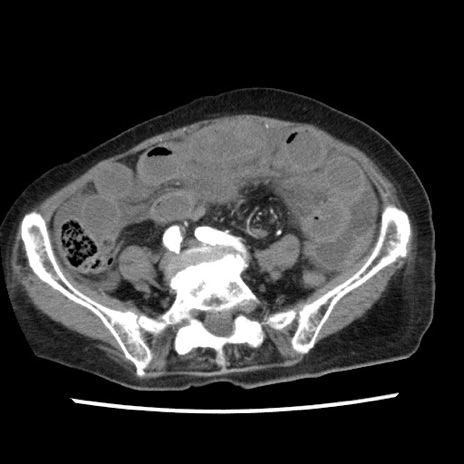

【症例】80歳代女性

【主訴】腹痛

【現病歴】8時間前から腹痛あり来院。

【既往歴】糖尿病、脂質異常症、子宮体癌にて子宮全摘術

【身体所見】意識清明・会話良好だが腹痛で苦悶様、全腹部にわたって反跳痛と圧痛あり

【データ】WBC 13600、CRP 0.14、LDH 224、CK 90